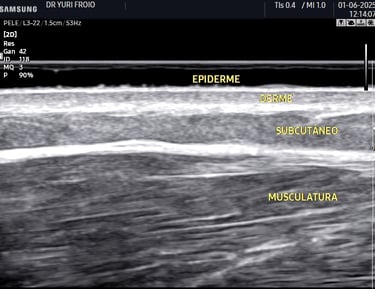

O ultrassom dermatológico é uma ferramenta avançada para avaliação da pele e tecidos subcutâneos. Permite analisar lesões, medir a espessura da pele e auxiliar no diagnóstico de tumores, cistos e inflamações. É um exame seguro, sem radiação e com alta precisão diagnóstica.